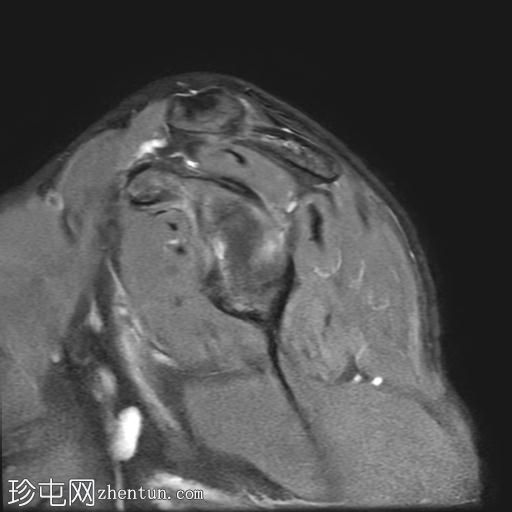

右肩外伤。

年龄:25岁

性别:男

矢状位PD加权像

脂肪抑制像

轴位PD加权像

Bankart损伤伴前盂唇及下方骨髓水肿

Hill-Sachs缺损表现为骨性压陷,肱骨头后外侧及下方骨髓水肿/挫伤

冈上肌腱关键区纤维肌腱病

MRI结果符合肩关节前脱位伴Hill-Sachs缺损和Bankart损伤的

影像

学表现。